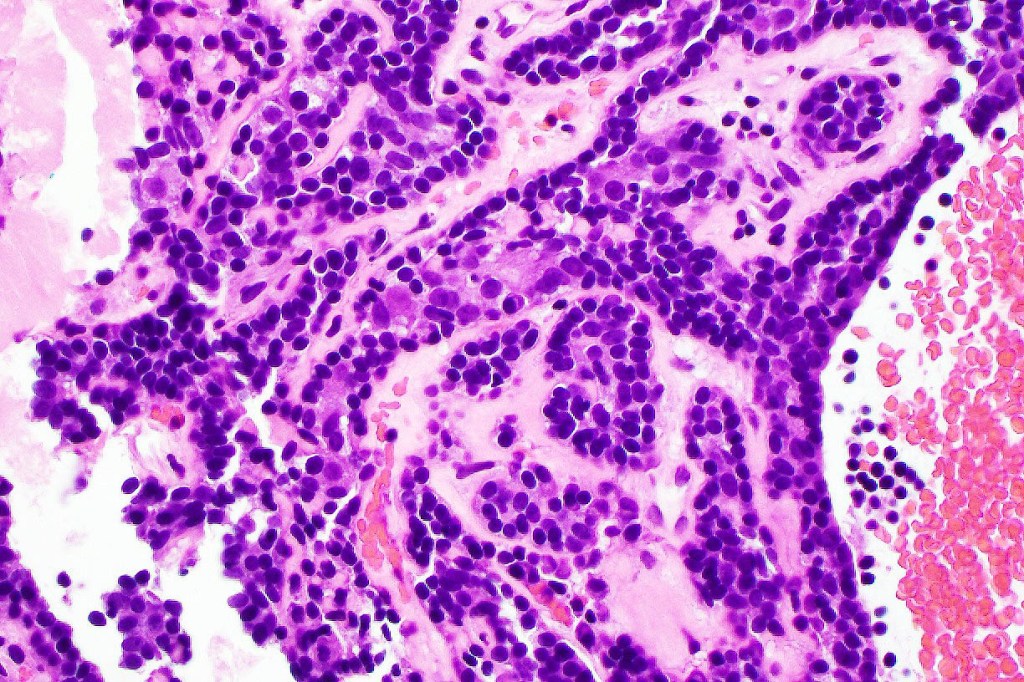

•Common association with an adjacent nerve & exceptional intraneural component

•Outer layer of small intensely basophilic cells surrounding larger pale staining or eosinophilic cells with vesicular nuclei & small nucleoli

•Ductal & exceptionally, glandular differentiation

•Spiradenocylindroma